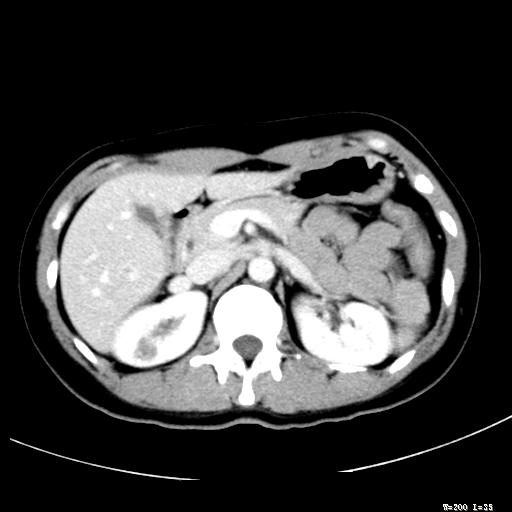

标题: CT25345:右肾占位。 [打印本页]

标题: CT25345:右肾占位。

女,30岁,右腰部胀痛3个月。

增强无明显强化,先考虑血管平滑肌脂肪瘤,建议作薄层扫描右mri检查,

增强无明显强化,先考虑血管平滑肌脂肪瘤,建议作薄层扫描右mri检查

感觉像囊肿.

囊肿!

考虑右肾近上极囊肿;建议必时行mri检查。